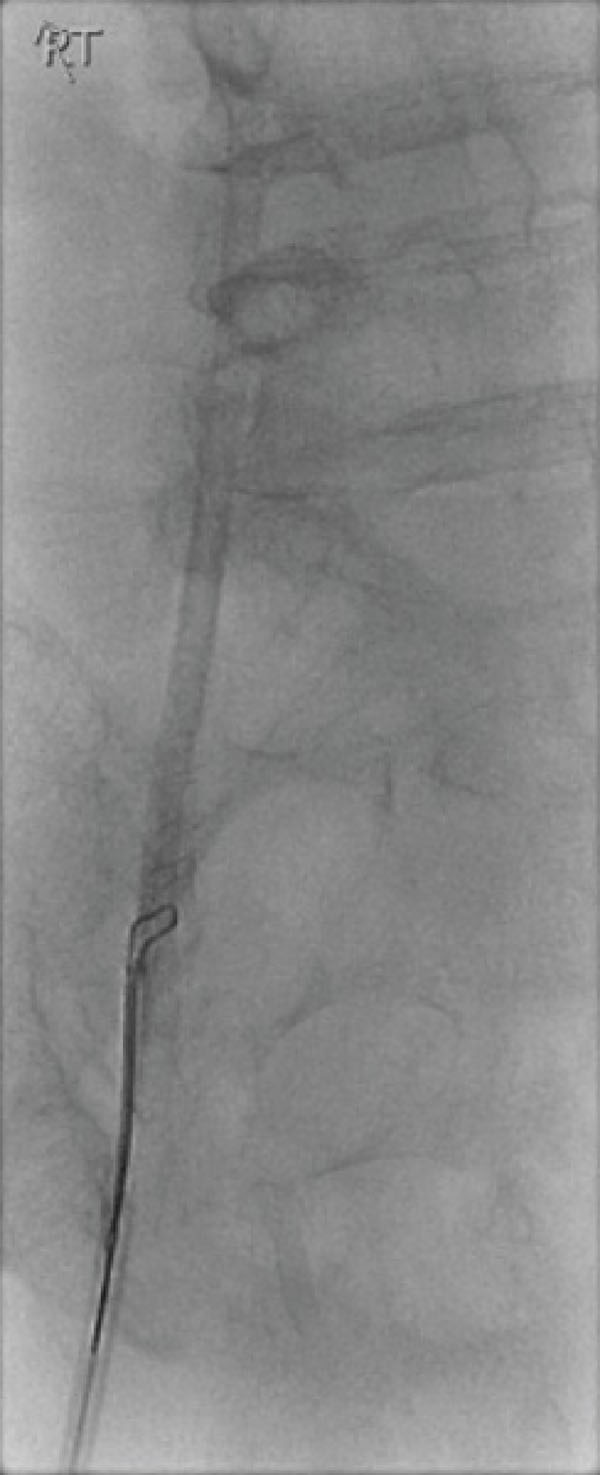

An urgent X-Ray revealed the catheter segment positioned in the superior vena cava (Fig. 1). The patient was transferred to the fluoroscopy suite and the severed segment of the catheter was retrieved using a snare device introduced via femoral vein (Fig. 2). There were no long-term complications.

Fig. (2).

The snare device deployed over the shaft of the catheter and removed via the femoral vein.